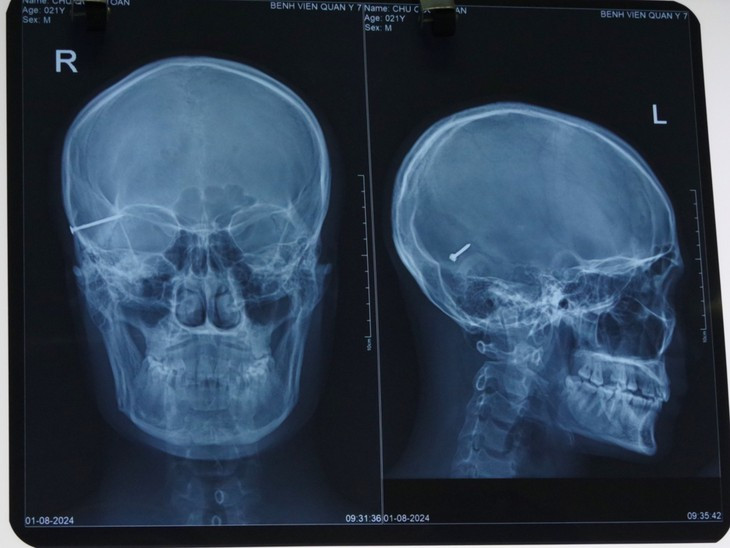

| Dị vật kim khí trong sọ bệnh nhân trên phim chụp - Ảnh BVCC |

Theo Thượng tá, BSCKII Trần Cao Thượng, Chủ nhiệm Khoa Chấn thương chỉnh hình cho biết: Sau 2 giờ đồng hồ phẫu thuật, dị vật đã được lấy thành công ra khỏi vùng sọ não của bệnh nhân. Đây được xem là một trong những ca mổ khó bởi vì dị vật là một chiếc đinh dài 4cm nằm ở vùng đầu, đòi hỏi trình độ kỹ thuật phức tạp của các y bác sĩ Bệnh viện Quân y 7.